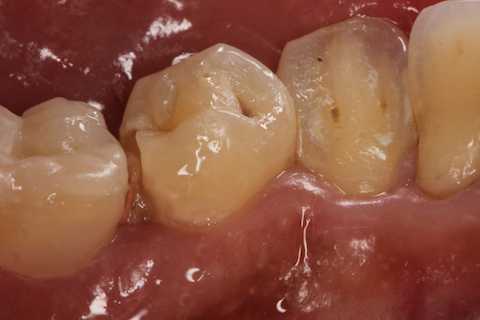

残根上のCR8 2025.10.28